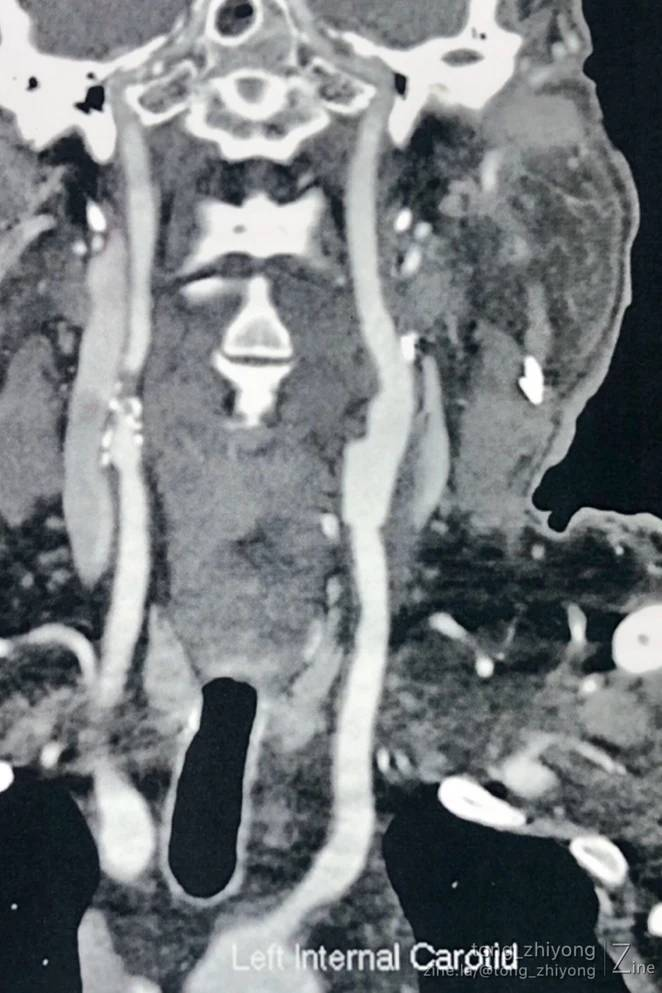

症状性左侧颈动脉重度狭窄

CTA确认:支架内重度再狭窄;

CTA确认:支架上端位于C2锥体上缘;颈内动脉内释放的6mm支架的直径“大于”远心端颈内动脉的直径。

显露到支架远心端颈内动脉,确认:颈内动脉内释放的6mm支架的直径“大于”远心端颈内动脉的直径。

术后一周CTA显示:颈部操作最上端到达C1锥体水平。钛结扎夹在CTA上像“香米粒”一样。

完全开通左侧颈动脉